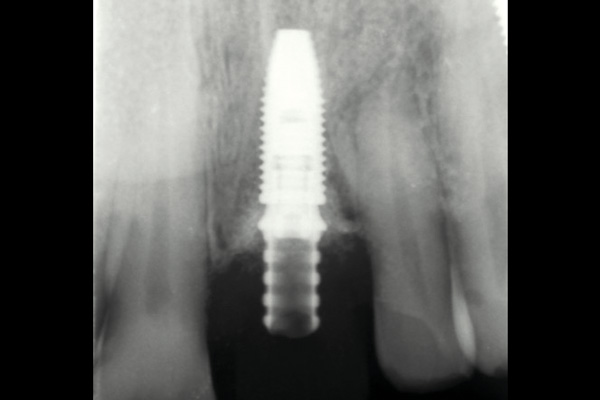

Preoperative Ortopantomogram of the teeth planned for extraction